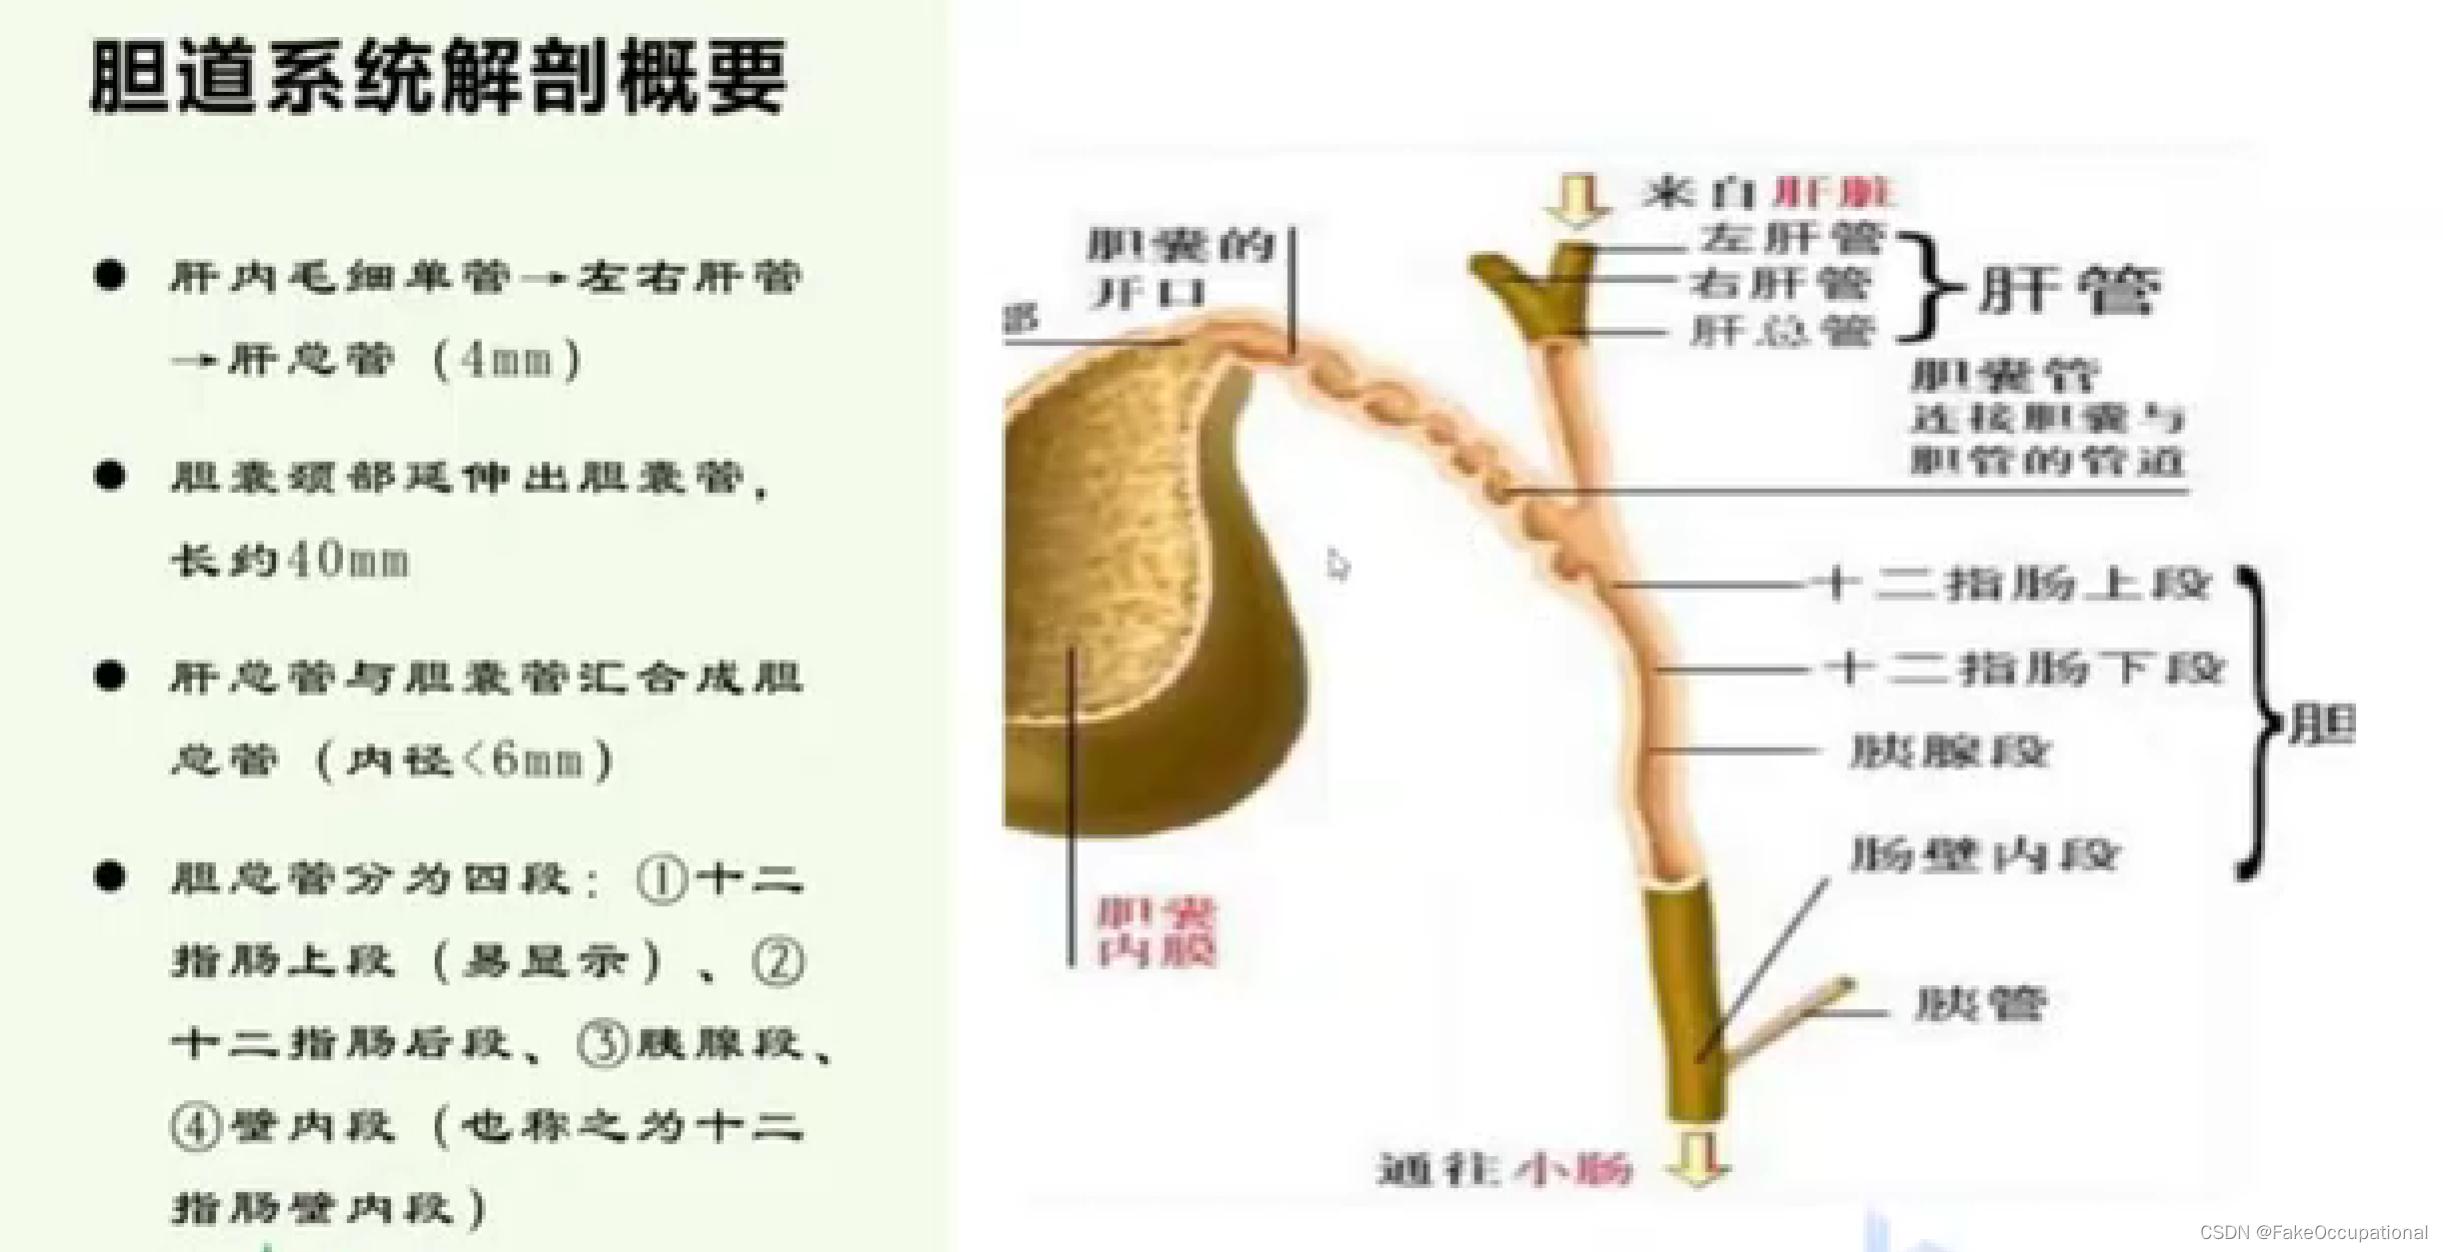

胆道系统解剖(和谐)

胰腺解剖及正常声像图

- 胰腺解剖与生理

腹膜后脏器 、无包膜、次于肝脏的大消化腺重约75克分内分泌部与外分泌部: 内分泌部分泌胰岛素,调节人体血糖浓度,外分泌部分泌胰液,有分解脂肪、蛋白质糖类的作用

位置: 胰腺的体表投影在脐上5cm-10cm处,位于第一第二腰椎体前方,胰尾直达脾门.形态和分部:分为头、颈、体、尾四部分。大致分为蜂料型(最常见) 、腊肠型、哑铃型,

主胰管起至胰尾横贯胰腺,在胰头部胰管和胆总管汇合,开口于十二指肠乳头。副胰管短细,超声难以显示